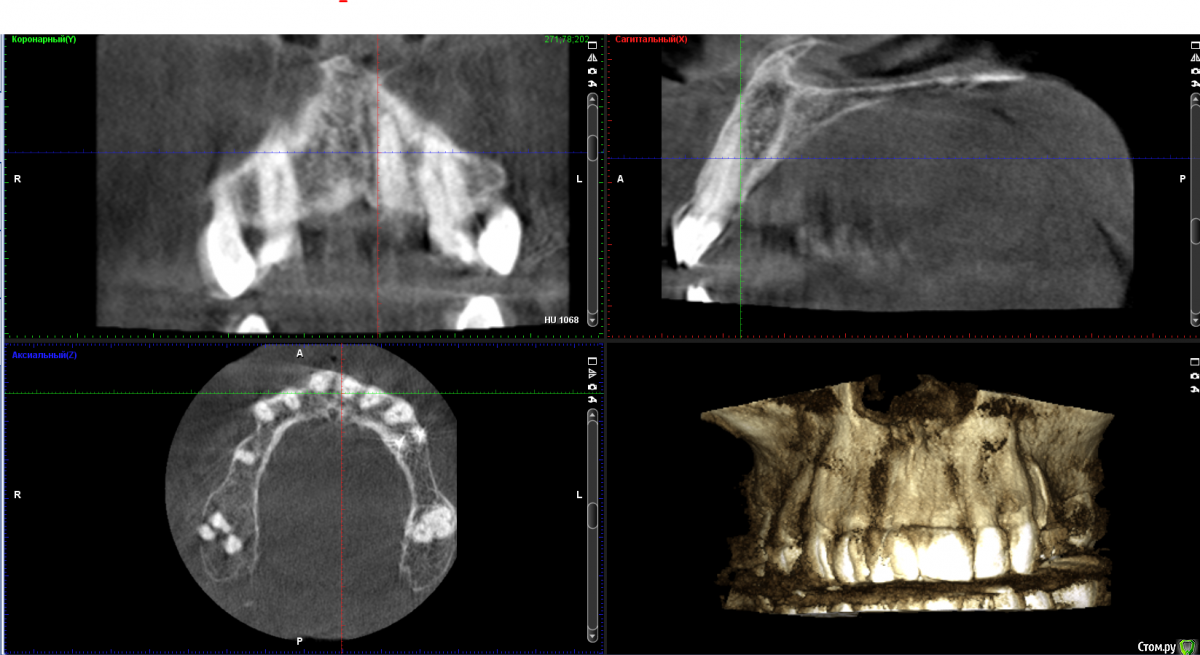

Дмитрий Л. Опубликовано 9 июня, 2018 Поделиться Опубликовано 9 июня, 2018 Я сам решил просто рассечь и удалить эту гадость но честно говоря смушают размеры и плюс случай такой первый раз лишний опыт не помешал бы.Спасибо.Научить чистить зубы.Рассекать смысла большого нет, может сильно кровить.Высечь до кости, бором или фрезой обработать +- милиметр кортикалки и под йодоформным тампоном провести.Гистология.Эндодонтия 21. 2 Ссылка на комментарий

Дмитрий Л. Опубликовано 11 июня, 2018 Поделиться Опубликовано 11 июня, 2018 Зачем? Зачем?! Будет дефект слизистой и оголённая кость. Как бы вы предложили вести такую рану? Как вы считаете, какая этиология эпулида в данном случае? Есть ли причинный зуб? Какой вообще диагноз и лечение вы бы предположили / предложили? Ссылка на комментарий

Irouil Опубликовано 11 июня, 2018 Поделиться Опубликовано 11 июня, 2018 На дворе вроде 21 век, зачем йодоформ? Большой дефект - лоскут, трансплантат, небольшой дефект - мобилизация, самозаживетизация. Я бы перед эндо как минимум провел ЭОД. Ссылка на комментарий

Дмитрий Л. Опубликовано 12 июня, 2018 Поделиться Опубликовано 12 июня, 2018 На дворе вроде 21 век, зачем йодоформ? Большой дефект - лоскут, трансплантат, небольшой дефект - мобилизация, самозаживетизация. Я бы перед эндо как минимум провел ЭОД.Да, здесь есть варианты, и я надеюсь автор темы не будет слепо следовать рекомендациям (в т.ч. моим). Ссылка на комментарий